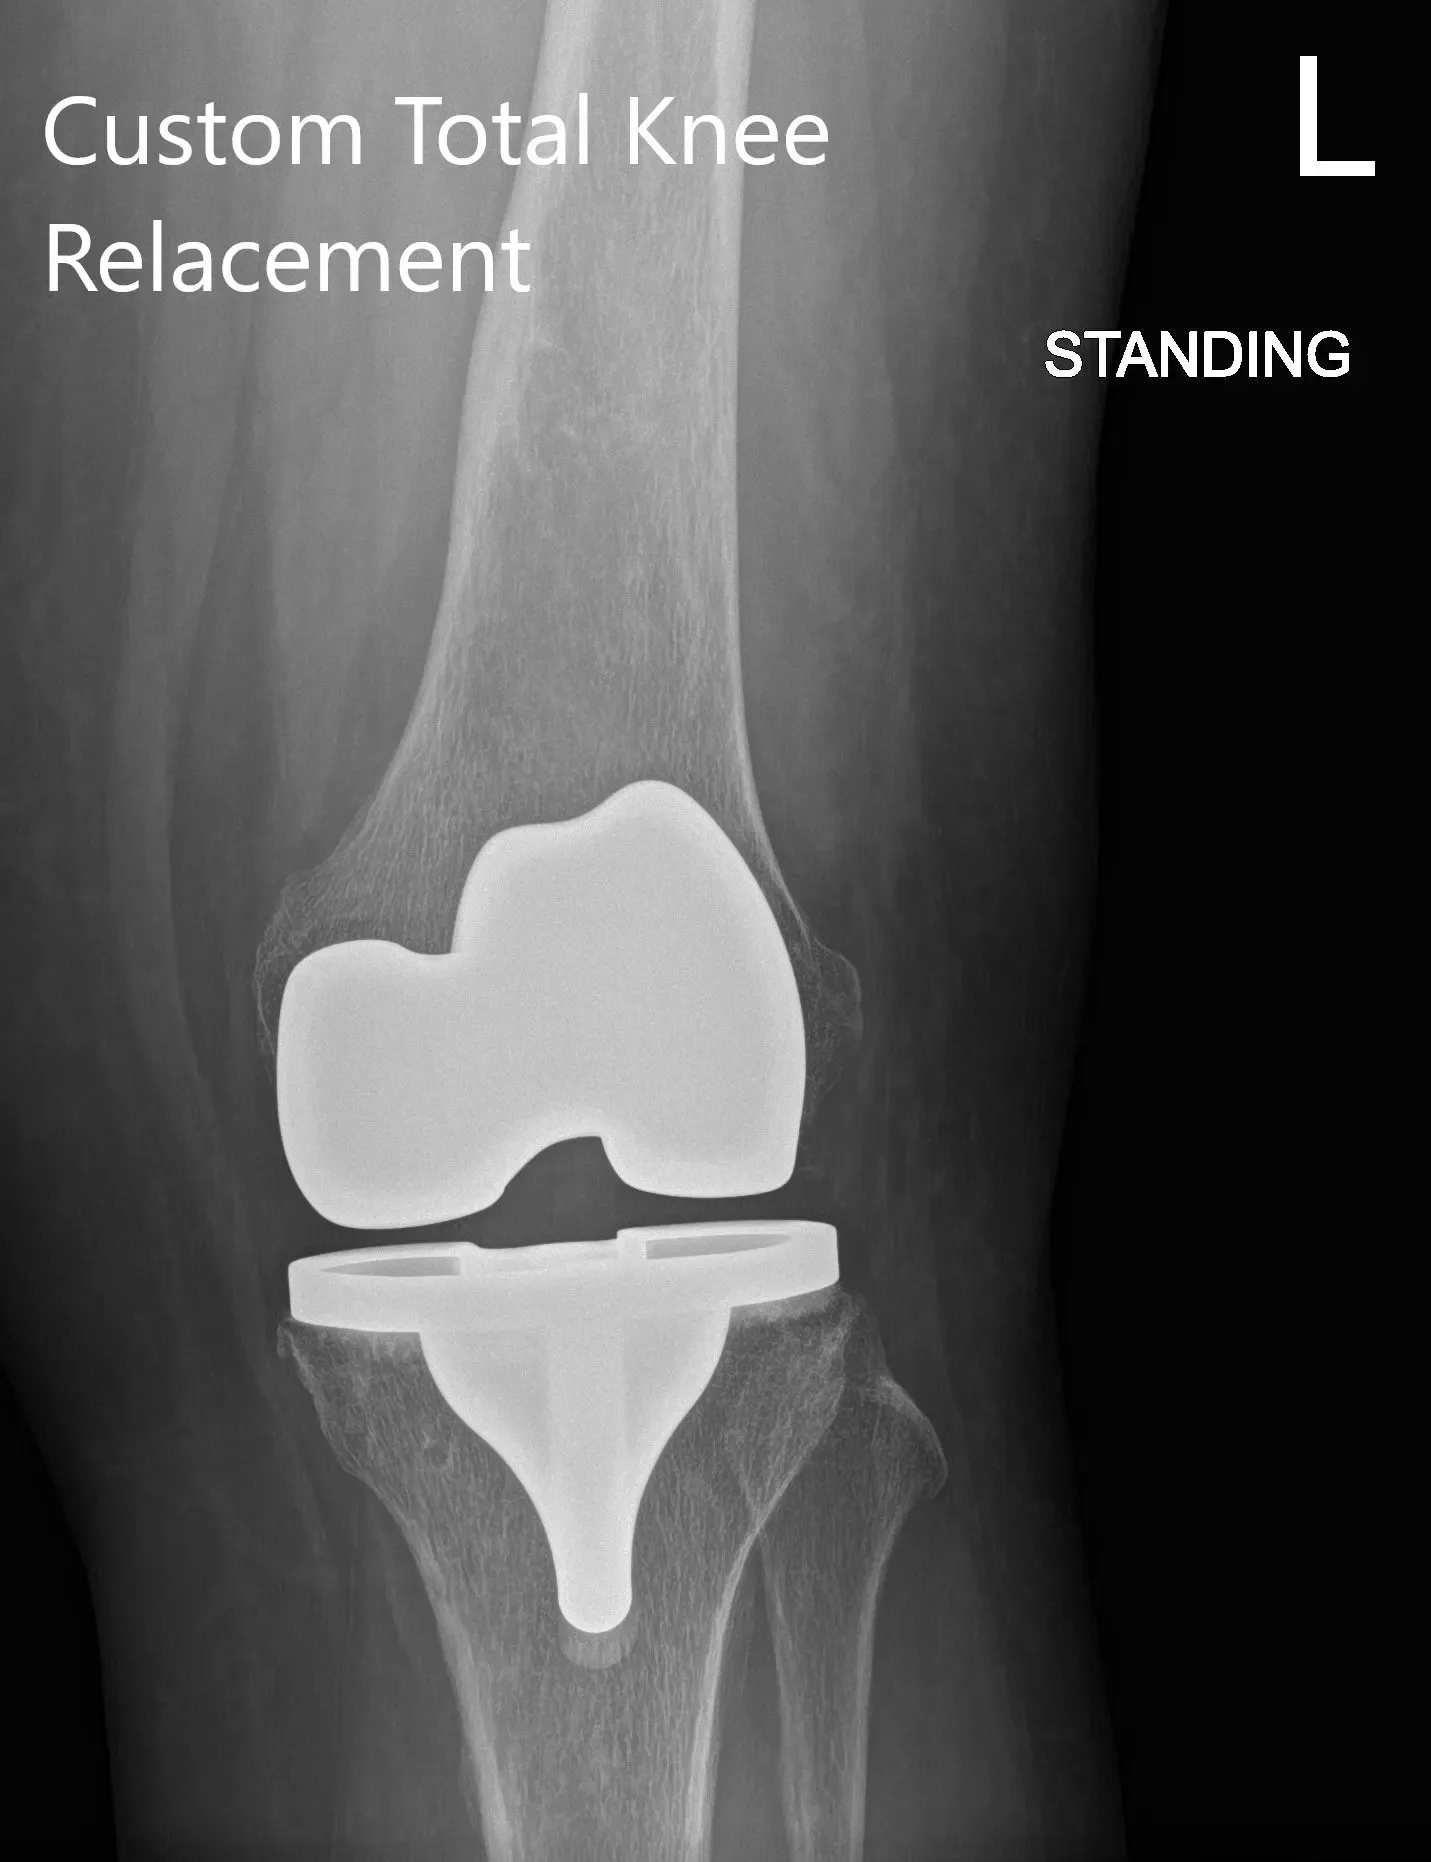

Radiografía postoperatoria que muestra PA y vista lateral de la rodilla izquierda

Tras la operación, caminaba ese mismo día y le empezaron a tomar aspirina para la profilaxis de trombosis venosa profunda. Tuvo un excelente alivio del dolor con manejo multimodal. Posteriormente, el paciente fue atendido para cambiar un vendaje estéril y su herida resultó seca, limpia e intacta. Se retiraron las grapas y el paciente mostró un rango completo de movimiento.

El paciente quedó extremadamente satisfecho con el resultado y, tras 3 meses, concluyó con éxito su fisioterapia. Desde entonces había vuelto a jugar al tenis y a ser voluntario en un hospital infantil. Pudo retomar su trabajo como enfermero y estuvo activo sin dolor ni rigidez. El paciente hace un seguimiento según sea necesario.